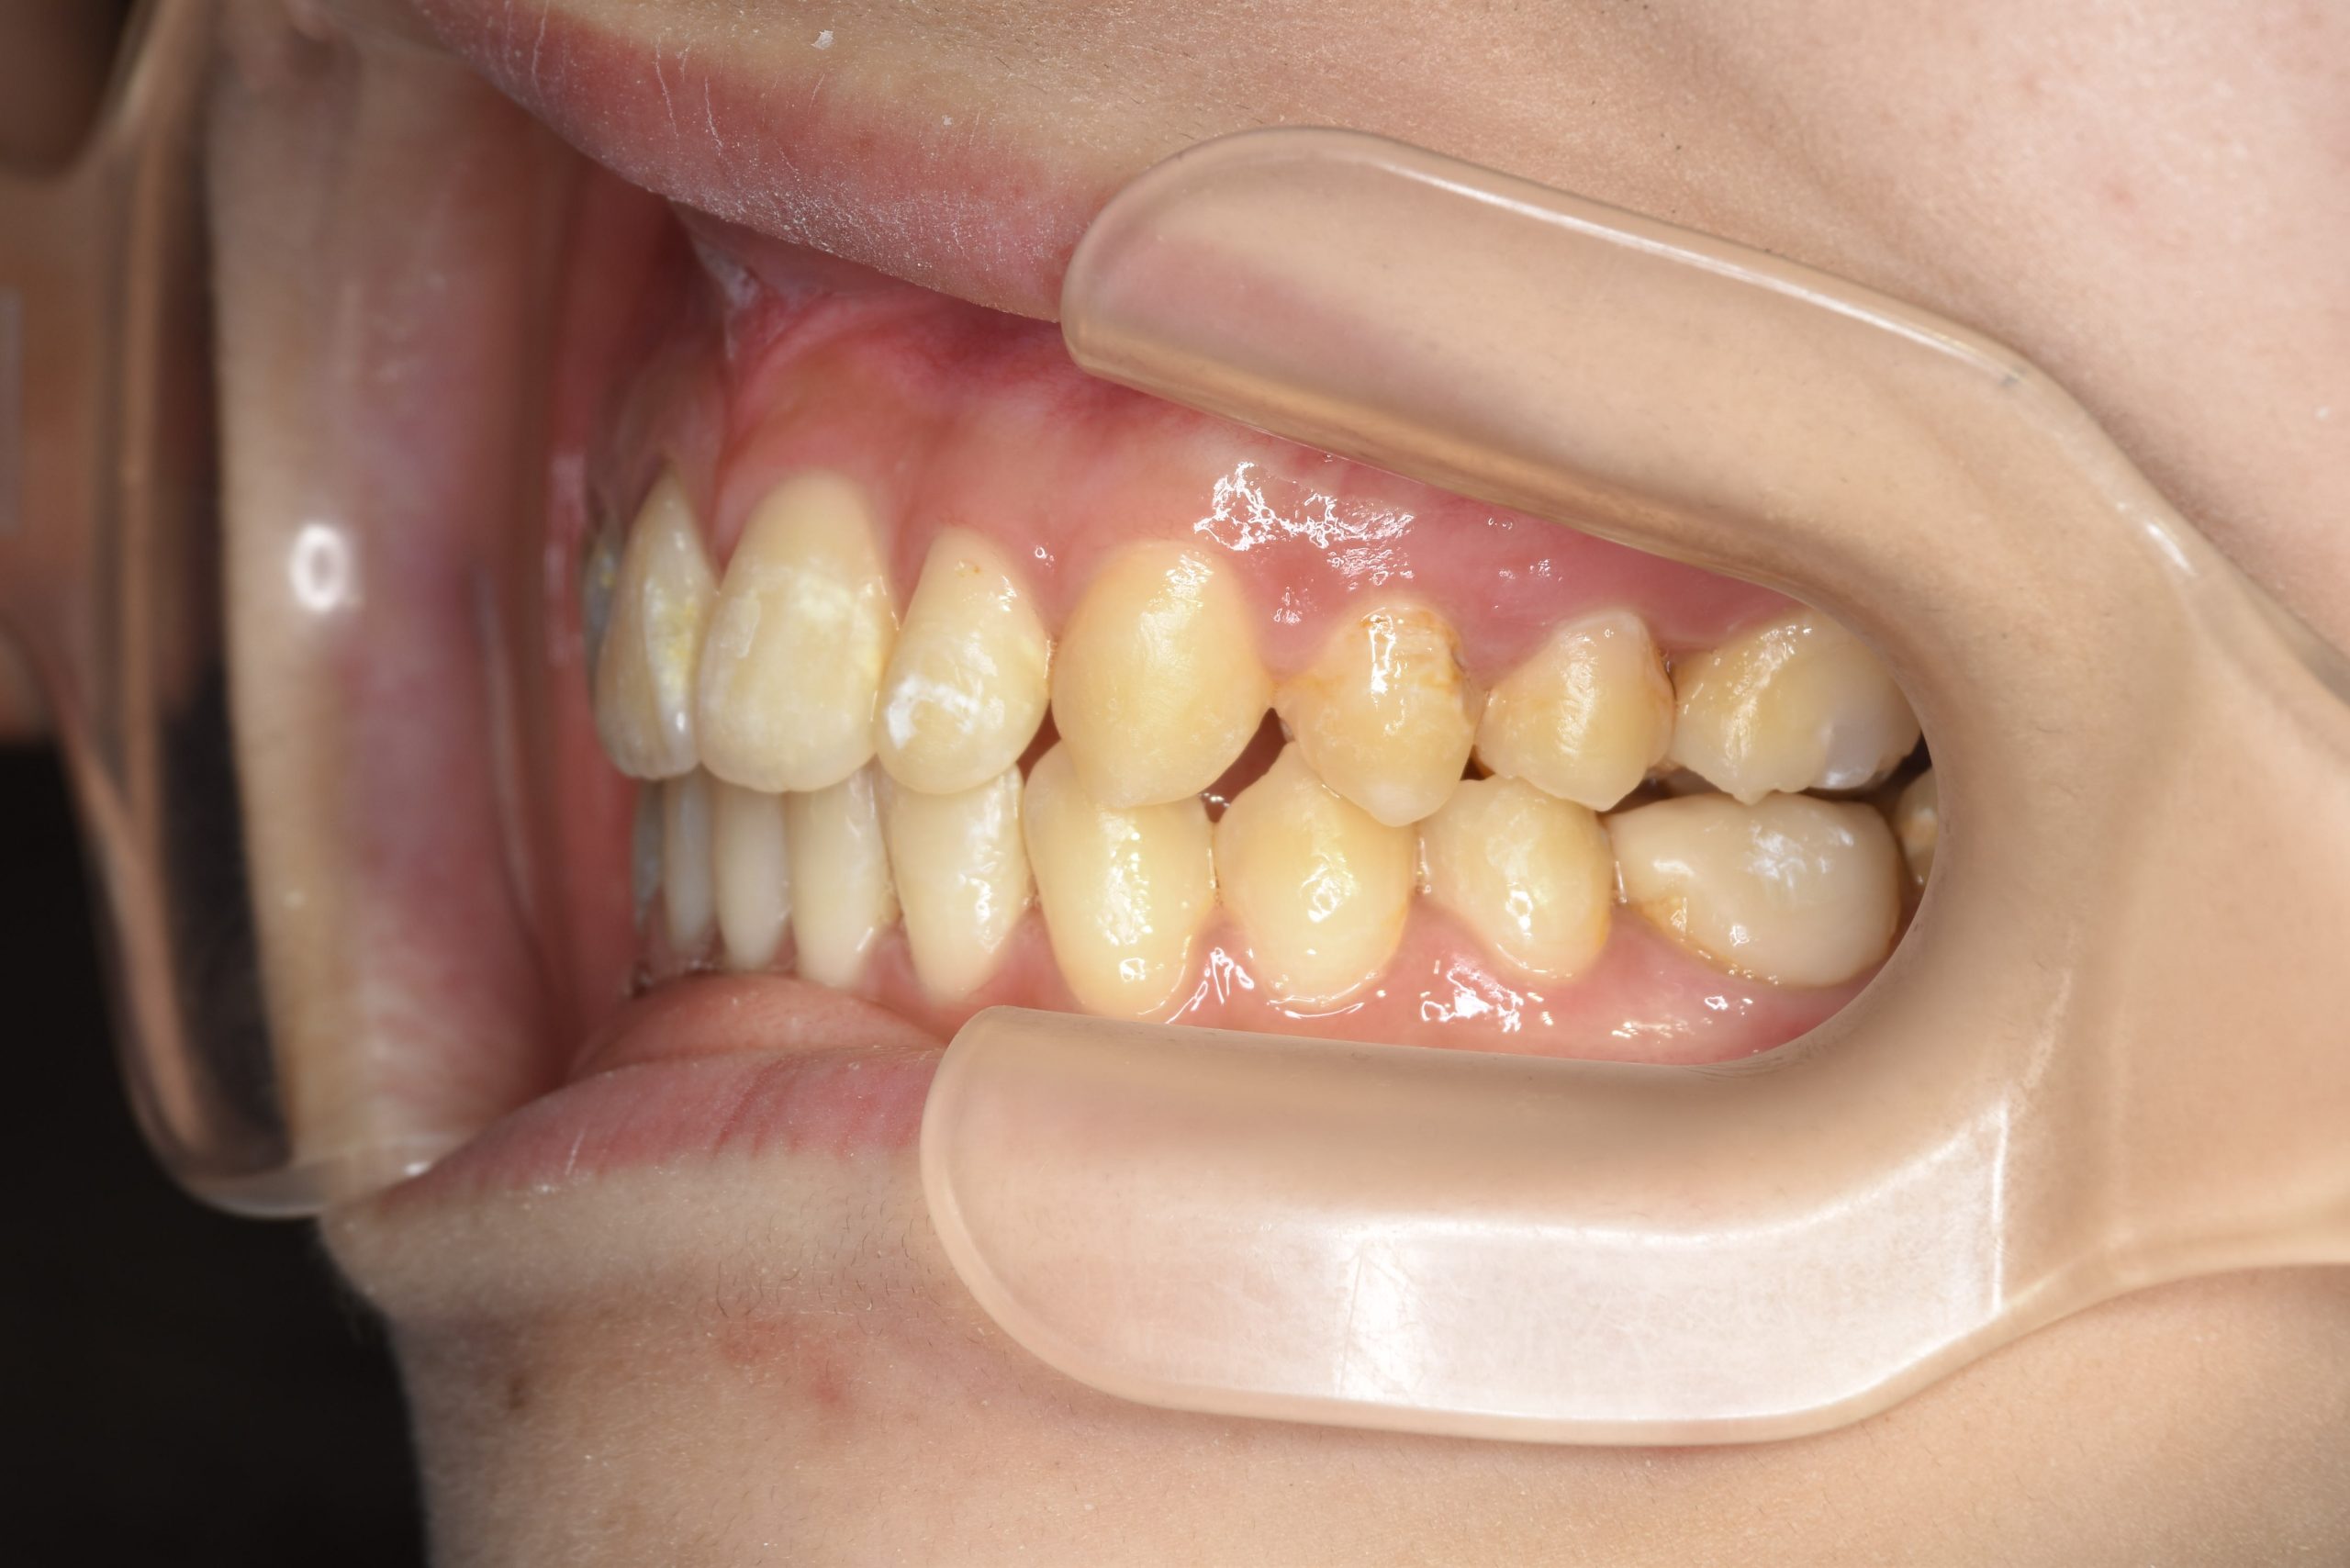

ビフォー

ワイヤー矯正治療|症例_032

主訴 歯並び|かみ合わせ

施術内容 MSEと下顎リンガルアーチを用いて上下顎骨を拡大した。

その後マルチブラケット装置を用いて非抜歯で歯牙を配列し良好な咬合を獲得した。

吸指癖と鼻閉症状は改善した。